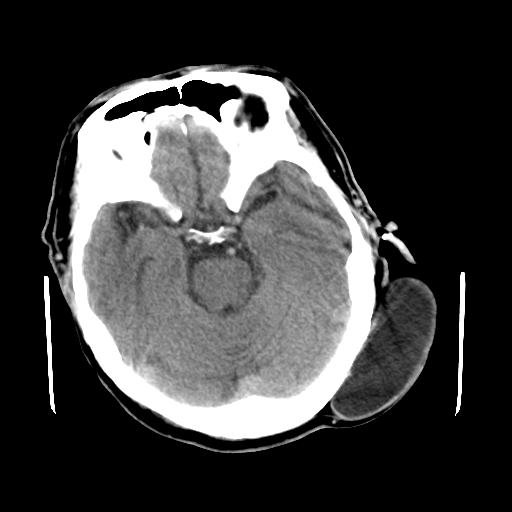

标题: CT25147:男,62岁,右侧肢体活动障碍不灵活三天。 [打印本页]

男,62岁,右侧肢体活动障碍不灵活三天,左侧头皮肿物十余年(ct值8hu)。

多发腔梗!皮下脂肪瘤!

1)多发性腔隙性脑梗塞。2)脑白质病。3)脑萎缩。4)左侧枕顶部头皮下皮样囊肿,不排除脂肪瘤。

1)多发性腔隙性脑梗塞。2)脑白质病。3)脑萎缩。4)左侧枕顶部头皮下皮样囊肿或表皮样囊肿。